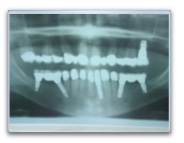

Ponts fixes postérieurs

Dans le cas ci-dessous, pour remplacer les 3 dents manquantes en bas à gauche et les 3 dents manquantes à droite, nous avons fabriqué 2 ponts de 3 dents sur 2 implants.